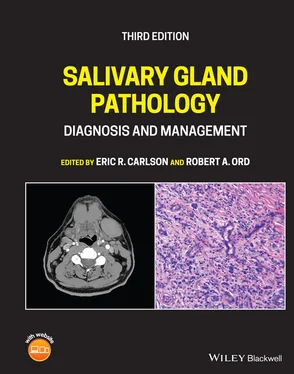

Figure 2.1. Axial CT of the neck in soft‐tissue window without contrast demonstrating poor definition between soft‐tissue structures. The blood vessels are unopacified and cannot be easily distinguished from lymph nodes. Note the sialolith (arrow) in the hilum of the left submandibular gland.